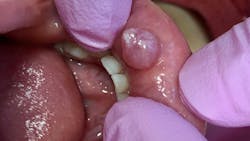

Patient: 66-year-old female

- 9 mm x 6 mm white, corrugated, irregular-bordered lesion

- Lesion located in upper right vestibular area

- Not tender to touch or palpation

- Not able to be removed or scraped off

- Large leukoplakic patch over erythematous tissue

Two weeks later …

- Lesion extended back toward first molar to mucolabial fold area